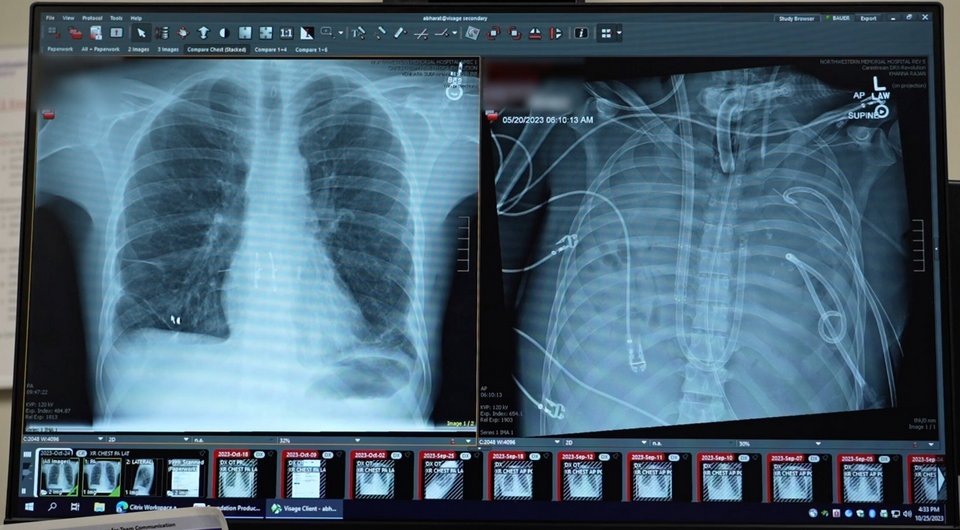

Американские исследователи сообщили о первом экспериментальном применении разработанного ими экстракорпорального полностью искусственного легкого. Аппарат позволил поддерживать жизнедеятельность и стабильное кровообращение 33-летнего пациента с удаленными легкими в течение 48 часов в ожидании трансплантации. Описание этого случая опубликовано в журнале Med.

Шанс испытать систему представился, когда в университетскую клинику поступил ранее здоровый 33-летний мужчина, у которого на фоне гриппа В развился ОРДС. В последующие шесть недель у него развилась быстро прогрессирующая некротизирующая пневмония, вызванная карбапенем-резистентной синегнойной палочкой (Pseudomonas aeruginosa), с двусторонними эмпиемами (скоплениями гноя в плевральной полости), требующими постоянного дренирования. Несмотря на антибактериальную терапию широкого спектра и полную венозно-артериальную ЭКМО у пациента периодически наступали перерывы в сердечной деятельности, свидетельствующие о рефрактерном септическом шоке. В силу этого врачи приняли решение удалить оба легких с обширной хирургической очисткой плевральных полостей, чтобы устранить источник инфекции и создать условия для возможной трансплантации.

Через 48 часов нахождения на искусственном легком пациенту выполнили двустороннюю трансплантацию донорских легких по стандартной технологии. Вирус гриппа В и синегнойная палочка у него определялись во время операции, но не после нее. Через три дня пациента отключили от ЭКМО, через неделю — от искусственной вентиляции и через восемь недель выписали из стационара. Чрезбронхиальные биопсии через 3, 6, 9 и 12 месяцев не выявили признаков острого отторжения, через 24 месяца трансплантат функционировал полноценно, функция внешнего дыхания была удовлетворительной, уплотнений и выпота на рентгенограмме грудной клетки не было. Патологоанатомическое исследование удаленных легких выявило обширный некроз и фиброз с диффузной инфильтрацией иммунными клетками и отложениями коллагена. Секвенирование РНК одиночных клеток и пространственный транскриптомный анализ подтвердили необратимые диффузные повреждения легких с тяжелым фиброзом.